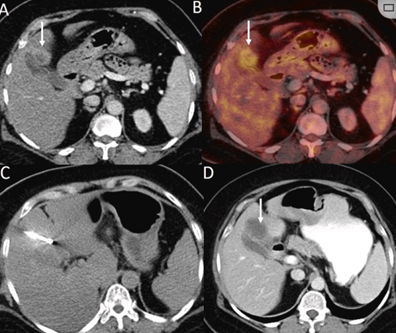

79 歲男性,肝轉移(結直腸癌)腫瘤的完全消融病例

(f)與基線(xiàn)影像(g)相比,12個(gè)月后的FDG-PET/CT顯示未見(jiàn)FDG攝取。

1個(gè)月后的軸向(e)和冠狀位(f)增強CT掃描顯示低密度區域,由于肉芽組織反應引起的邊緣增強。